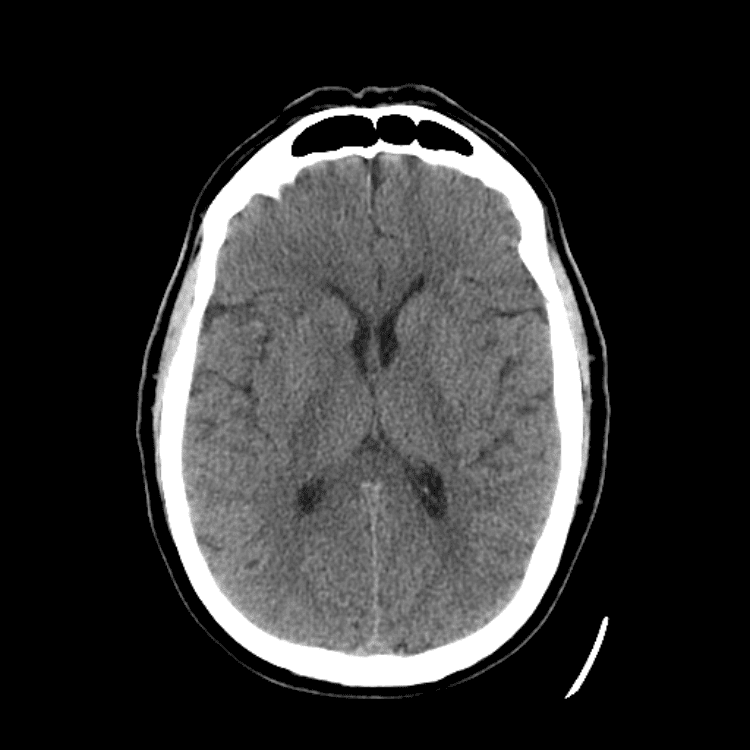

Nontraumatic Brain

Classic